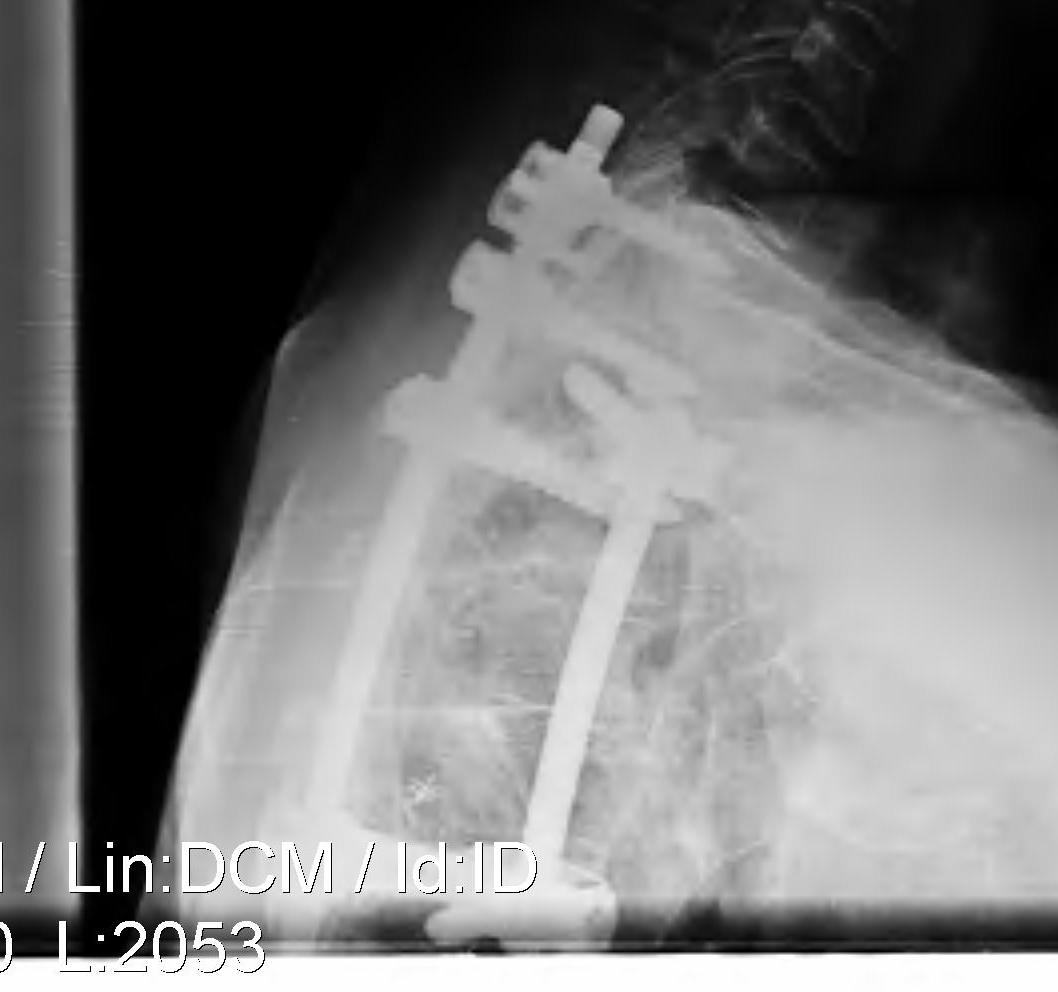

B. Thoracotomy and Corpectomy

Indication

- 2 level disc protrusion

Technique

Thoractomy Approach

- loin incision

- removal of rib 2 levels above

- through bed of rib

- extrapleural approach

- from left to avoid IVC

Tie off segmental artery on one side

- disc convex, body concave

- allows access to disc protrusion

- discectomy + / - corpectomy as required for exposure / 2 level disc

- anterior +/- posterior stabilisation if corpectomy

- if simply remove disc may not need stabilisation especially in elderly

- will autofuse